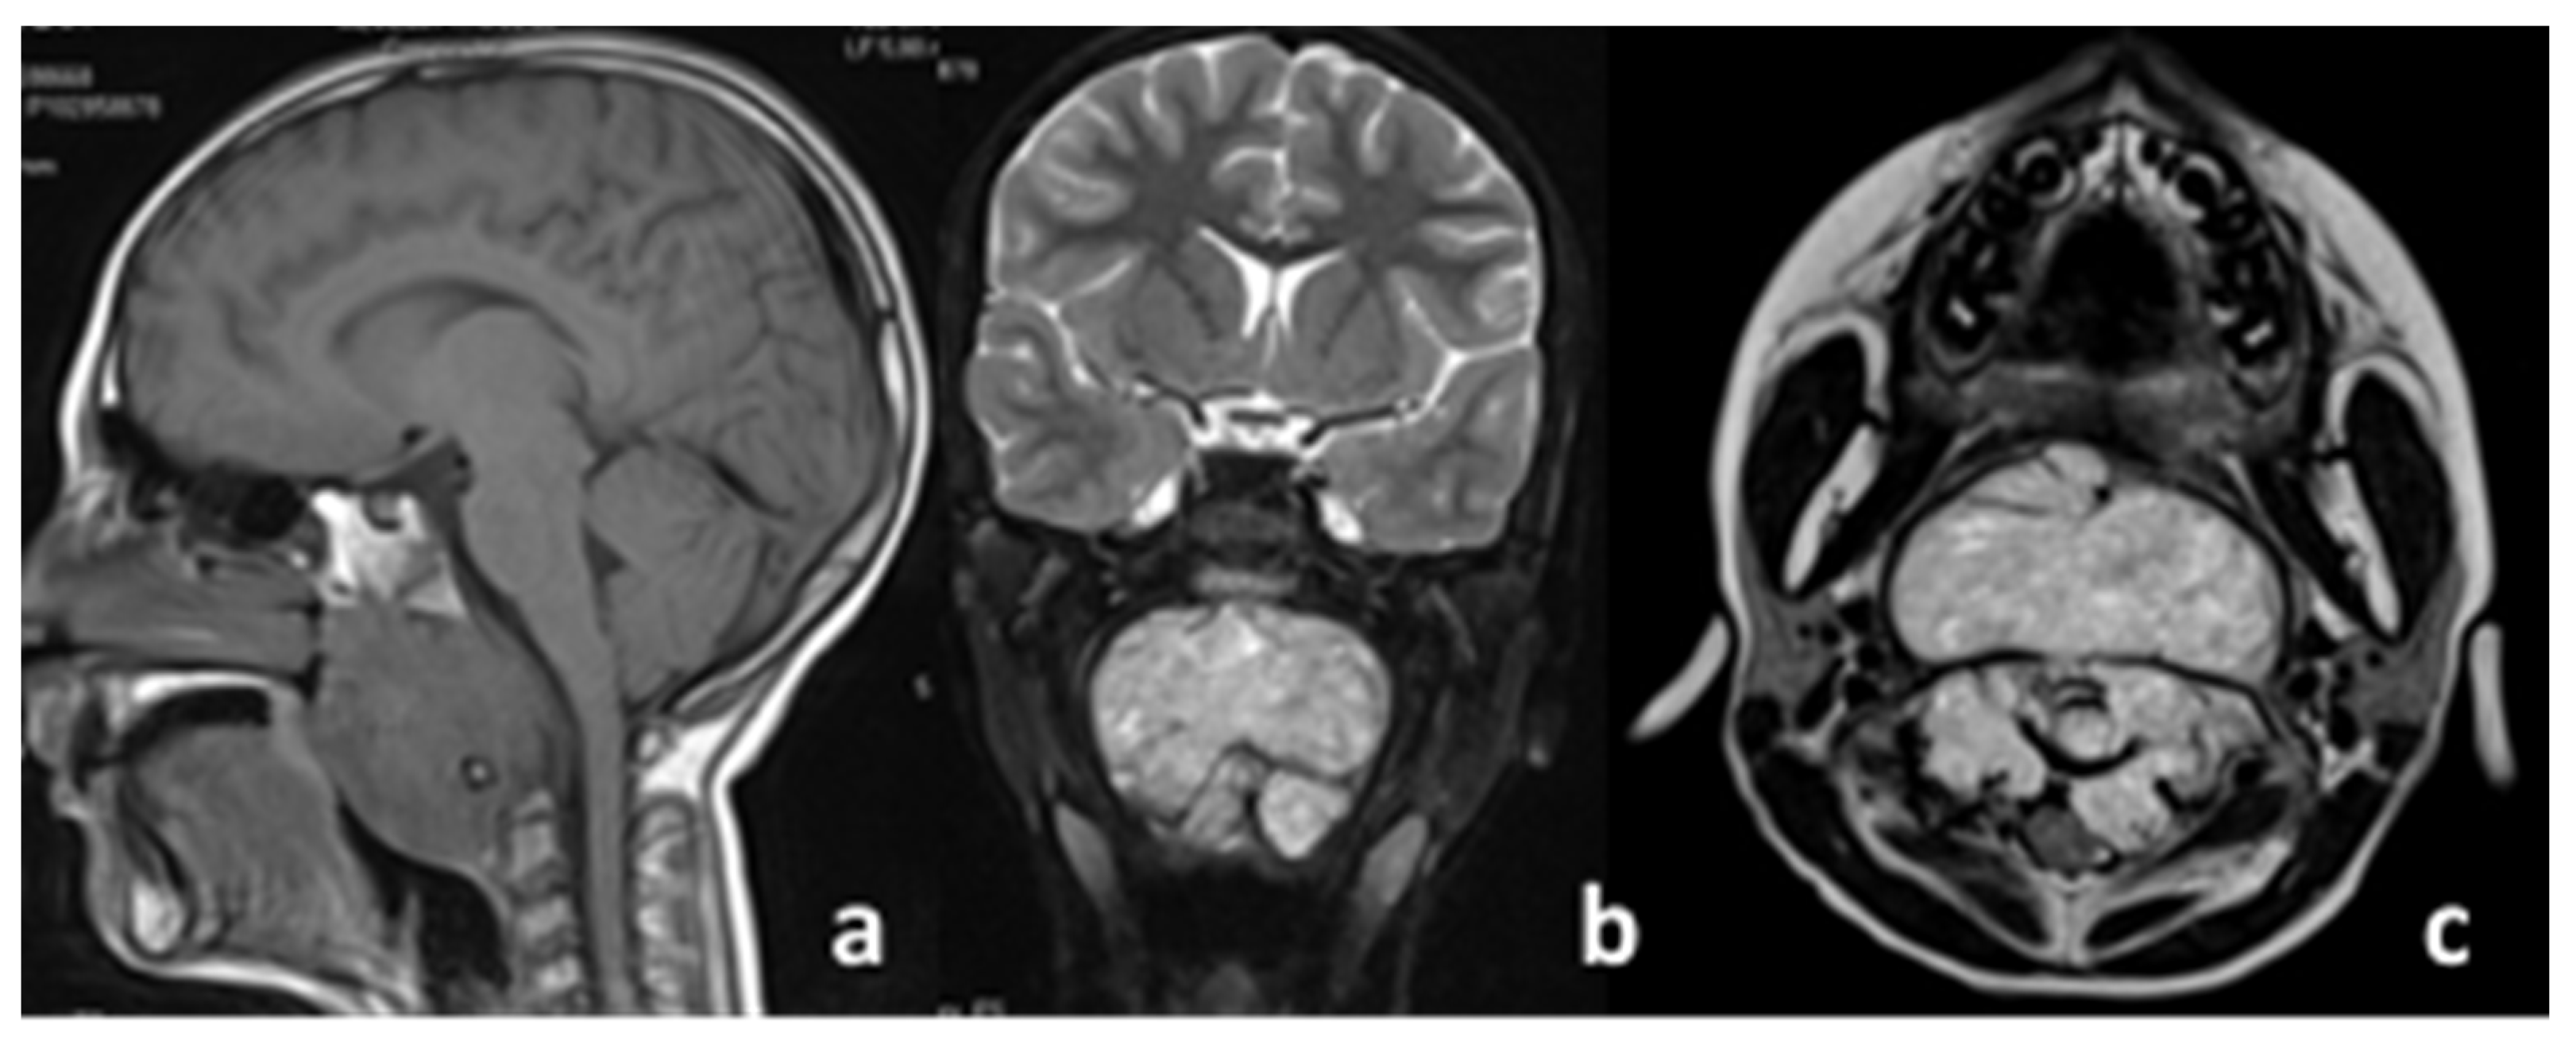

Figure 2 “a” and “b” show the axial T2-weighted MRI with the macroscopic residual of the disease post-surgery, just before the beginning of proton therapy treatment.

As can be seen in the top image, the disease was present bilaterally on the tooth of the axis and was characterized by two different MRI-signaled components in T2, with one component being frankly hyperintense in T2, typical of the radiological signal of the classic histology upon the right condyle (thin red arrow in Figure 2a,c).

One nodule component was non-homogenous hypo–hyperintense in T2 and was represented by a left para-medullary bulb with compression and a shift on the spinal cord (thick red arrow in the Figure 2b); such a feature is less common in the classic type of histology but is more typically present in de-differentiated chordomas (it is possible that it can appear in post-surgical resection) [7,8]. The histological picture is of a neoplasm composed by chords and strands of tumor cells embedded in a myxoid background. The tumor cells show abundant pink cytoplasm and round regular nuclei with little cytological atypia. Some cells show multiple cytoplasmic vacuoles creating the classic bubbly appearance of physaliferous cells. On immunohistochemical examination, the neoplasm appears diffusely immunoreactive for cytokeratin and EMA and shows nuclear immunoreactivity for brachyury and variable S100 positivity. A diagnosis of conventional chordoma was made.

Figure 2. Pre-proton therapy images (representative T2-weighted MRI axial views (a) and (b)) and histologic examination after biopsy at the first diagnosis (c).